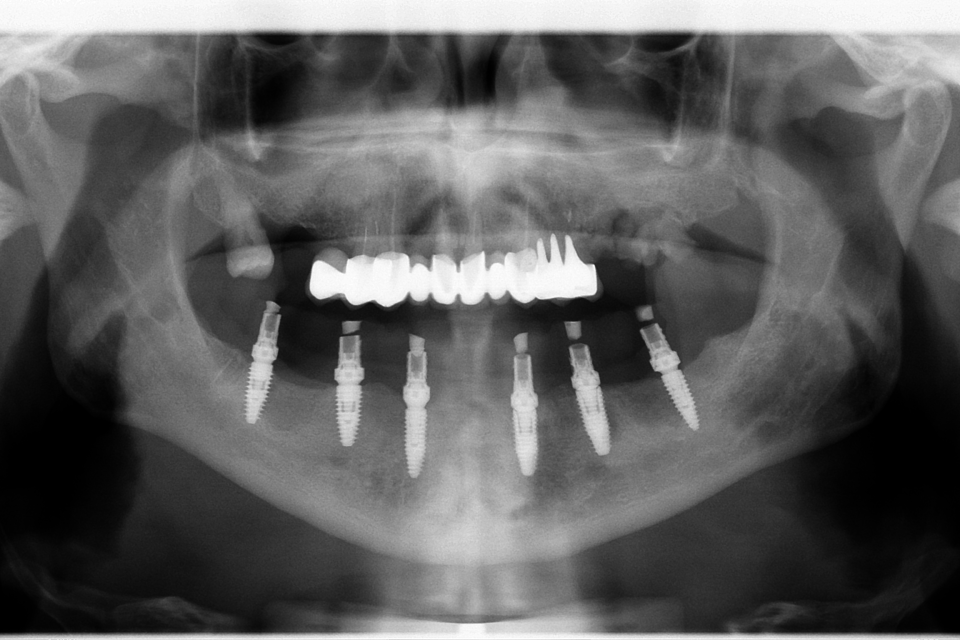

All on 6 protezate cu ajutoul unei lucrări din zirconiu pe suport de titan

All on 6 protezate cu ajutoul unei lucrări din zirconiu pe suport de titan.

Imaginile sunt prezentate în ordinea evoluției tratamentului, de la situația inițială la rezultatul final.